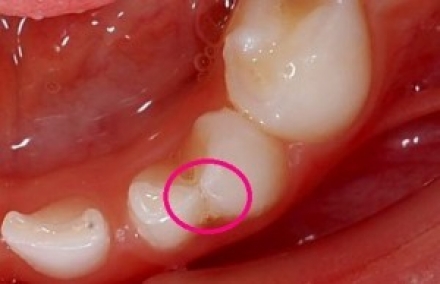

〈癒合している境目が虫歯になりやすい〉

癒合している歯の境目は溝になり、プラーク(歯垢)がたまりやすく、虫歯になりやすいです。また、磨きにくいことから、歯茎の周りに汚れがたまり、炎症を起こすこともあります。